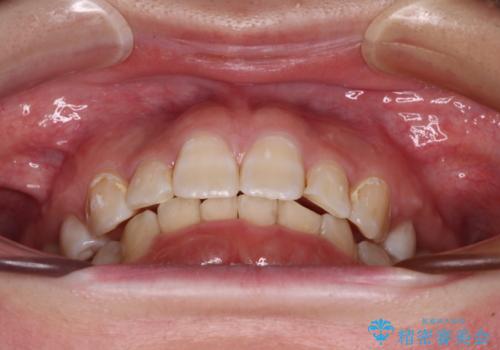

著しい八重歯を短期間で改善 ワイヤー装置による抜歯矯正

- 八重歯と下顎小臼歯の欠損を気にして来院された患者様です。

下顎小臼歯の欠損により過蓋咬合となっていたため、下顎は臼歯を起こすことで咬み合わせを改善し、八重歯は第一小臼歯2本を抜歯し、補助装置を使用して速やかに改善することとしました。

著しい過蓋咬合の改善が必要であった割には、治療期間は2年強と標準的でした。

八重歯は3,4か月で速やかに改善されました。